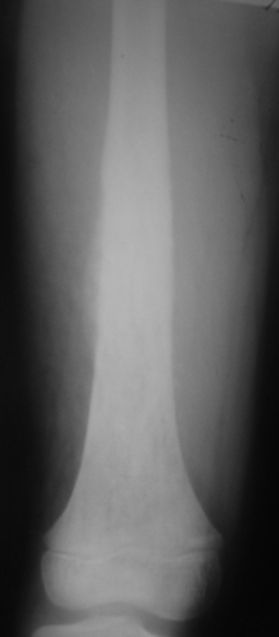

Мальчик 8 лет. Жалобы на боли в левом бедре. Со слов мальчика, ударился бедром несколько недель назад, после чего и начались боли.

В общем-то, диагноз сомнения не вызывает злокачественная опухоль, вероятнее всего - остеогенная саркома. У нас возникла дискуссия по поводу того, нужно ли брать открытую биопсию для гистологического подтверждения диагноза, либо сразу направить ребёнка в специализированный центр. С одной стороны, диагноз должен быть подтверждён гистологически. С другой - каждое нерадикальное вмешетельство на опухоли увеличивает вероятность метастазирования. В литературе чаще встречается такой подход - пациента сразу направляют в специализированный центр, где ему проводят как биопсию, так и дальнейшее лечение. Хотелось бы узнать мнение уважаемых коллег.

It could be Ewing sarcoma-its diaphyseal

Судя по представленным снимкам, нужно подумать о саркоме Юинга, так как Остеогенная саркома редко поражает диафиз трубчатых костей. Ее излюбленно место - метаэпифиз.